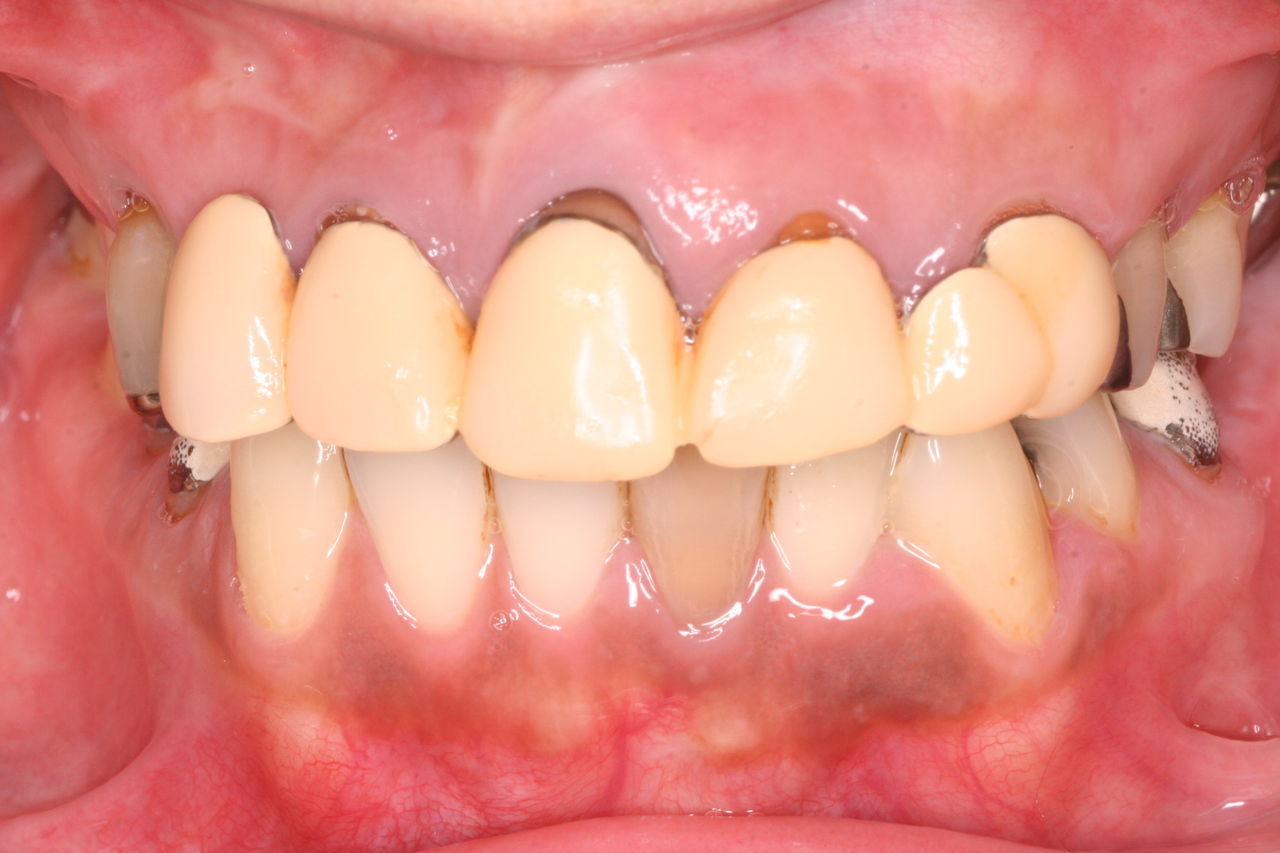

前歯の根っこの治療を終了して仮歯を入れたところです。

上からみると向かって左側のみダミーの部分があり、かり歯を入れた右側は仮歯の大きさで隙間をふさいでます。

上下の真ん中の線も不一致ですので、矯正治療で可能な限り顔面の真ん中と歯の真ん中が一致するように努力します。